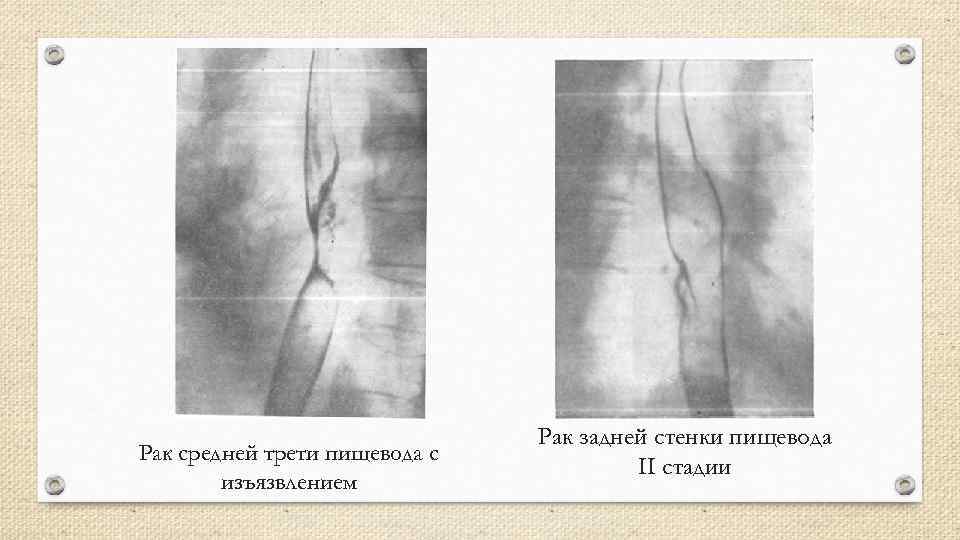

Рак средней трети пищевода с изъязвлением Рак задней стенки пищевода II стадии

Рак средней трети пищевода с изъязвлением Рак задней стенки пищевода II стадии